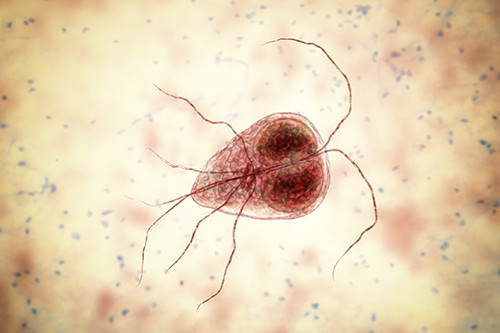

Vaincre la Giardiose : Guide de Traitement, Symptômes et Hygiène Canine

Vaincre la Giardiose : Guide de Traitement, Symptômes et Hygiène Canine

Vaincre la Giardiose : Guide de Traitement, Symptômes et Hygiène Canine